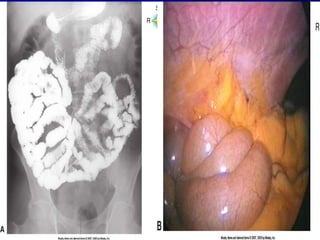

Intestino Grueso Dimensiones del intestino grueso—diametro promedio es de 6 cm y su longitud es de aproximadamente 1.5-1.8 m Divisiones del intestino grueso  Cecum o ciego—primeros 5-8 cm,saco ciego en el cuadrante inferior derecho  Colon Colon ascendente—esta en posicion vertical en el lado derecho del abdomen extendiendose hasta el borde inferior del higado(angulo hepatico); la valvula ileocecal permite el paso del material del ileon al intestino grueso pero no en sentido contrario Colon transverso --cruza horizontalmente el abdomen por debajo del higado, estomago y bazo (angulo esplenico) pero por encima del intestino delgado. Se extiende desde el angulo hepatico hasta el angulo esplenico Colon descendente—esta en posicion vertical en el lado izquierdo del abdomen,por debajo del bazo hasta el nivel de la cresta ileaca Colon sigmoide—une el colon descendente al recto Rectum—ultimos 17-20 cm (7-8 pulgadas) del tracto GI;los ultimos 2.5cm del recto constituyen el canal anal y la apertura del conducto al exterior es el ano

Intestino Grueso Dimensionesdel intestino grueso—diametro promedio es de 6 cm y su longitud es de aproximadamente 1.5-1.8 m Divisiones del intestino grueso Cecum o ciego—primeros 5-8 cm,saco ciego en el cuadrante inferior derecho Colon Colon ascendente—esta en posicion vertical en el lado derecho del abdomen extendiendose hasta el borde inferior del higado(angulo hepatico); la valvula ileocecal permite el paso del material del ileon al intestino grueso pero no en sentido contrario Colon transverso --cruza horizontalmente el abdomen por debajo del higado, estomago y bazo (angulo esplenico) pero por encima del intestino delgado. Se extiende desde el angulo hepatico hasta el angulo esplenico Colon descendente—esta en posicion vertical en el lado izquierdo del abdomen,por debajo del bazo hasta el nivel de la cresta ileaca Colon sigmoide—une el colon descendente al recto Rectum—ultimos 17-20 cm (7-8 pulgadas) del tracto GI;los ultimos 2.5cm del recto constituyen el canal anal y la apertura del conducto al exterior es el ano